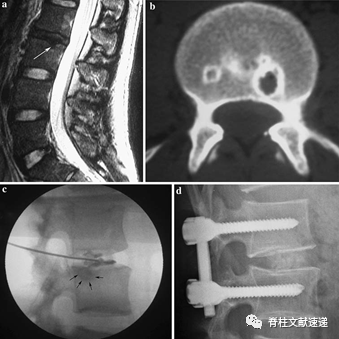

结果显示:当对影像学检查判定为终板损伤性病变并排除纤维环撕裂的患者行椎间盘造影术时,与相邻正常的椎间盘相比,当造影剂流入终板缺损处时,患者均会产生定位准确的疼痛刺激,当对造影术显示的病变节段行椎间融合术后,如下图所示,21位患者术前VAS腰痛评分5.3-9.1,平均7.15;术后VAS腰痛评分0-5;平均1.64;术后VAS评分较术前显著降低。术后ODI评分较术前显著降低。

图注:a.26岁男性患者,腰痛4年,MRI检查示L2/3椎间盘退变和L3上终板存在终板损伤性病变(Schmorl 结节,白色箭头处);b.CT结果显示L3椎体上终板有圆形损伤病变;c.椎间盘造影显示造影剂流入L3上终板损伤性病变处(黑色箭头处),同时产生剧烈的疼痛刺激;d.患者行L2-3后路腰椎椎间融合椎弓根螺钉固定术,术后腰痛症状消失。